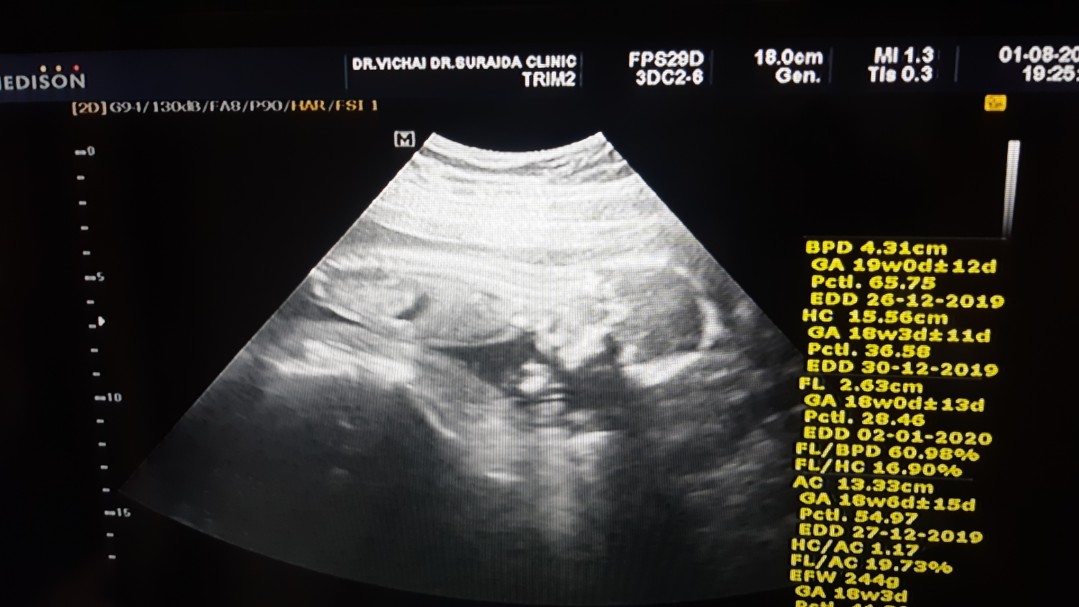

18 week 3 day

Post reply image